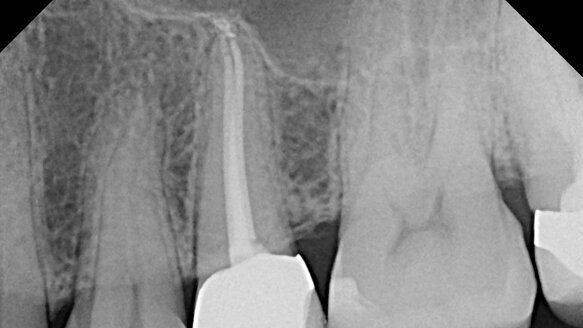

The AAE also provides general practitioners with many educational resources that encourage high standards of endodontic care and support collaboration. Treatment Options for the Compromised Tooth: A Decision Guide includes case examples with radiographs of successful endodontic treatment in difficult cases and is designed to encourage general dentists to assess all possible endodontic treatment options before recommending extraction. The Case Difficulty Assessment and Referral Form can be used to evaluate a patient’s condition and assess risk factors that may affect the outcome of treatment. Biannual mailings and online archives of the ENDODONTICS: Colleagues for Excellence newsletter highlight clinical topics of interest to dentists who perform their own endodontic treatment and benefit from coverage of best practices and the latest advancements in the specialty.